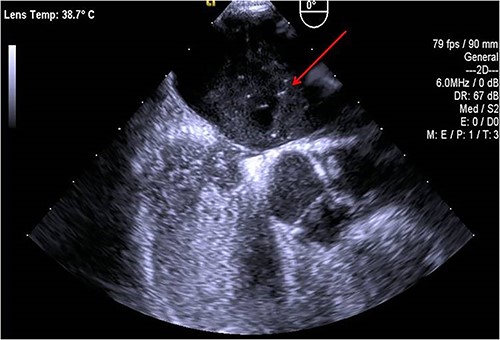

A 45-year-old female patient with a personal history of hypothyroidism, obesity, inferior parathyroidectomy for parathyroid adenoma and adnexectomy for benign ovarian cystadenoma presented with sudden onset dyspnoea as well as with pain, poikilothermia, pallor and weakness of left upper limb and hand. Physical examination showed peripheral O2 saturation of 80% and absence of radial and left brachial pulses. On Duplex ultrasound, deep or superficial vein thrombosis was not identified. On thoracic computed tomography angiography, bilateral pulmonary embolism (PE) and occlusion of the axillary artery were identified while aortic dissection was excluded (Fig.1). Given the concomitant upper limb ischemia and PE, the patient was hypocoagulated with low-molecular-weight heparin and underwent urgent thromboembolectomy and angiography, through a distal brachial surgical approach. Postoperatively, the patient recovered a radial and ulnar pulses. The embolic source was further investigated by transthoracic and transesophageal echocardiography, which identified a PFO (Fig.2). The patient was discharged on rivaroxaban for anticoagulation (20 mg once daily). During follow-up, thrombophilia screening was performed, including antiphospholipid antibody syndrome, factor V Leiden mutation, prothrombin gene mutation, antithrombin III defect, protein C and S deficiency assessments, but all results were negative. Considering the single event of right atrioventricular overload and flow-inversion through PFO associated with PE, PFO closure was not indicated.

The diagnosis of cardiac defect can be performed by transthoracic or transesophageal echocardiography. Transthoracic echocardiography is a noninvasive and easily accessible examination but has a low sensitivity compared to the transesophageal technique for the diagnosis of PFO. In the case described, the diagnosis was made by transesophageal ultrasound, associated with a ‘bubble test’ (involves the delivery of saline mixed with air into a vein to assess the flow of blood through the heart) following an unconclusive transthoracic ultrasound.